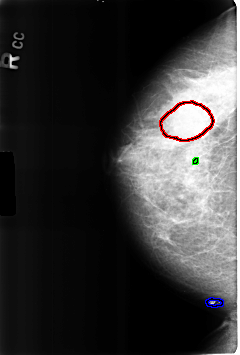

FILE: B_3226_1.RIGHT_CC.OVERLAY TOTAL_ABNORMALITIES 3 ABNORMALITY 1 LESION_TYPE MASS SHAPE OVAL MARGINS CIRCUMSCRIBED-OBSCURED ASSESSMENT 2 SUBTLETY 3 PATHOLOGY BENIGN TOTAL_OUTLINES 1 BOUNDARY ABNORMALITY 2 LESION_TYPE CALCIFICATION TYPE COARSE DISTRIBUTION N/A ASSESSMENT 2 SUBTLETY 3 PATHOLOGY BENIGN_WITHOUT_CALLBACK TOTAL_OUTLINES 1 BOUNDARY ABNORMALITY 3 LESION_TYPE CALCIFICATION TYPE COARSE DISTRIBUTION N/A ASSESSMENT 2 SUBTLETY 3 PATHOLOGY BENIGN_WITHOUT_CALLBACK TOTAL_OUTLINES 1 BOUNDARY |